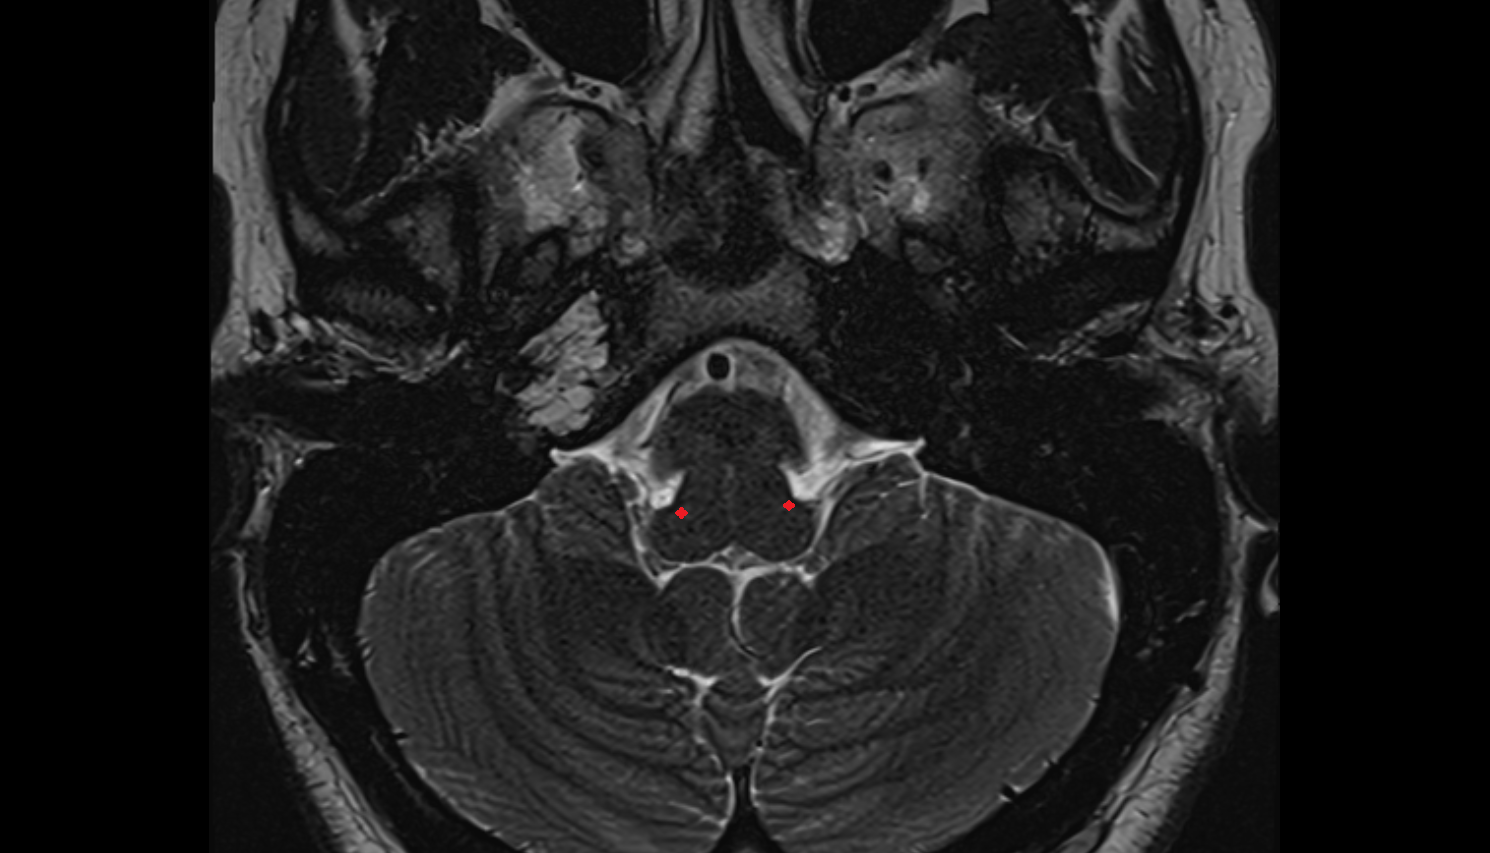

- Middle cerebellar peduncle

- Fourth ventricle

- Lateral aperture of fourth ventricle (foramen of Luschka)